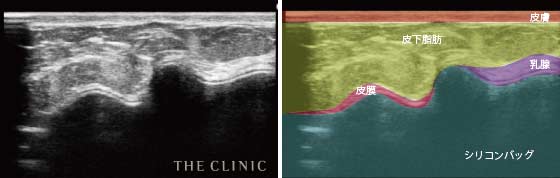

乳腺や脂肪、筋肉などの層の状態をみることができるので、シリコンバッグのまわりにある皮膜の厚さや石灰化の状態だけではなく、シリコンバッグが挿入されている正確な位置やシリコンバッグの破損なども確認することができます。

- 正常な状態のシリコンバッグ

- 正しい位置に正常なシリコンバッグが位置している状態